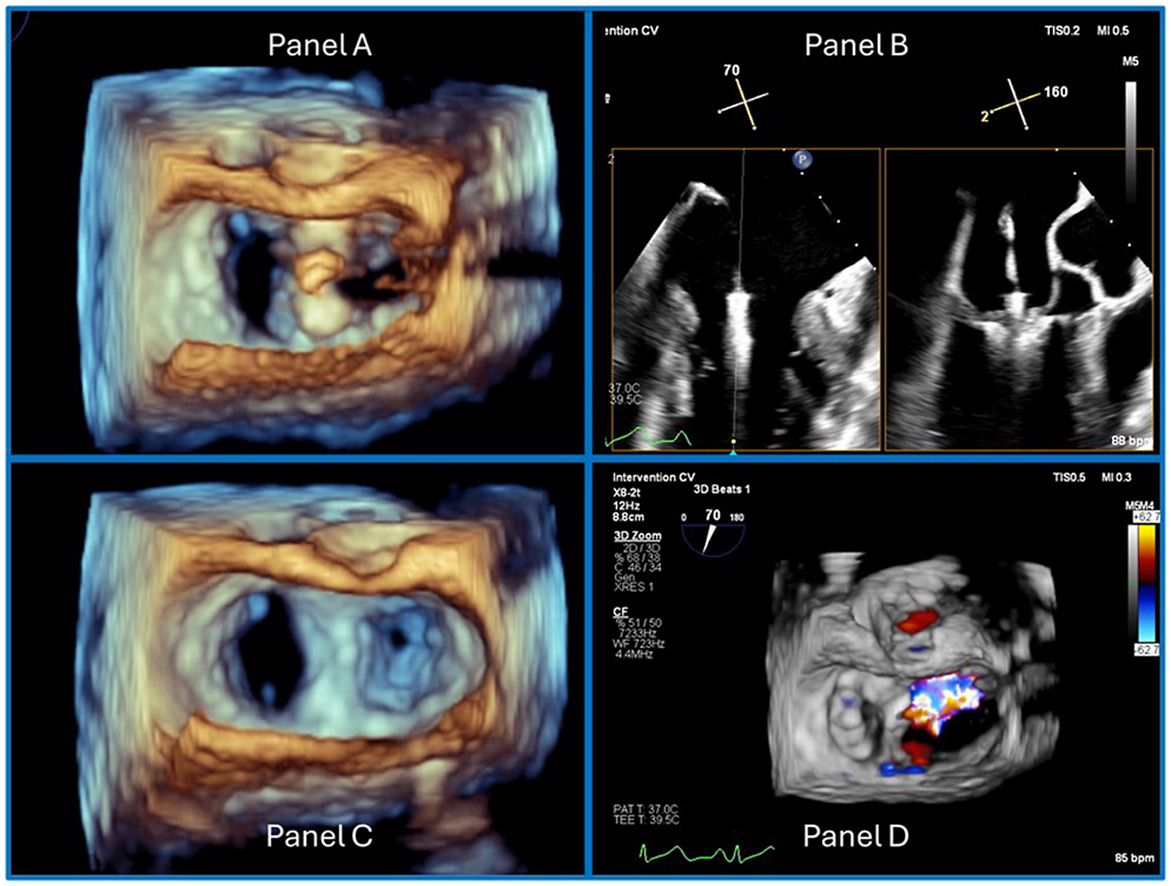

June CASE: Just Useful, Noteworthy Examples

June 17, 2025

Announcements